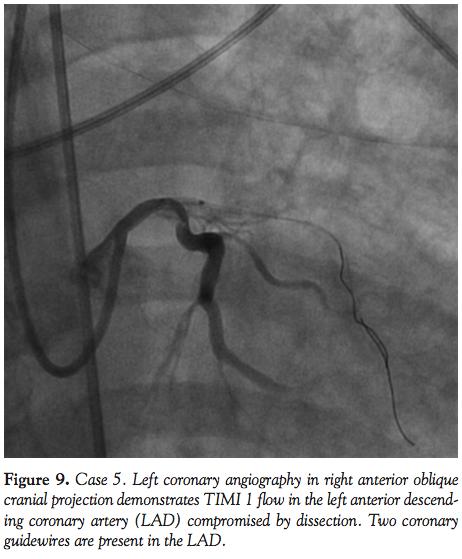

Case 1. A 56-year-old female with no past history and complaining of dyspnea, chest tightness, and profound weakness for 3 hours was brought to the hospital by paramedics. Her pre-hospital electrocardiogram (ECG) demonstrated an acute anterior STEMI. On hospital arrival, she was hemodynamically stable with a blood pressure of 140/67, though she required intubation for respiratory distress. Moments before transport to the catheterization laboratory, she experienced a PEA cardiac arrest requiring CPR and administration of

epinephrine and atropine before her pulse was restored. She suffered recurrent cardiac arrest in the CCL and resuscitation efforts were initiated with CPR, epinephrine, and atropine. The LUCAS device was placed and mCPR commenced. An IABP was placed via the right femoral approach and a temporary transvenous pacemaker placed via the right femoral vein. Angiography was performed via left femoral access during mechanical CPR. Her mid LAD was occluded with TIMI 0 flow (Figure 1). Balloon angioplasty was performed promptly with rapid restoration of TIMI 3 flow and placement of a bare-metal stent in the mid LAD (Figure 2). The semi-radiolucent LUCAS device was not visible on coronary angiography or during PCI in a steep right anterior oblique cranial projection. Despite maximal support with an IABP and multiple vasopressors, the patient manifested no significant myocardial function and expired in the catheterization laboratory after mCPR was discontinued.

Fluoroscopic and cineangiographic imaging during mCPR with the LUCAS device requires few significant adjustments. The images presented here represent one center’s experience and diagnostic images were obtained in all cases. Anterior-posterior projections are limited by the height and radio-opacity of the LUCAS drive unit over the patient’s chest. Straight right and left anterior oblique views provide adequate visualization despite the back-brace component of the device being visible on fluoroscopy. As evidenced in Cases 1 and 4, significant cranial angulation (>30°) can provide coronary imaging without visual encroachment by the device components.

In animal models, cerebral blood flow during CPR is improved with mCPR,15 and mCPR devices provide significantly higher coronary perfusion pressures than manual CPR.16 Coronary flow assessment has been reported in both animal models and human subjects.16,17 In 4 out of 6 patients studied by Larsen et al with TIMI 3 flow during mCPR, invasive measurements documented adequate coronary perfusion pressure gradients. In the present experience, coronary flow during mCPR is pulsatile, but classification by TIMI grade is readily apparent. In Cases 1, 4, and 5, the PCI procedure itself was performed during mCPR compressions (Figures 1, 2, 8, and 10).